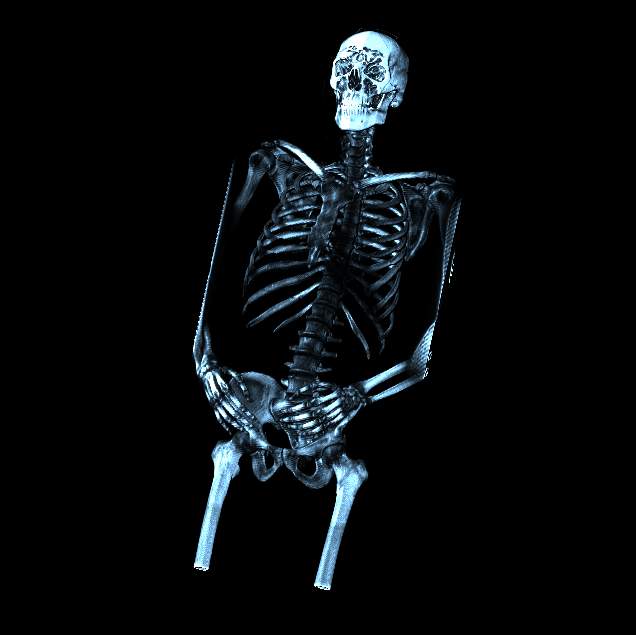

Visible human male CT data

Shaded whole

body with bone

Data Resolution : 512x512x1294